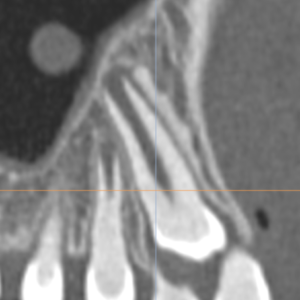

Le dégagement chirurgical de dents incluses​

On constate parfois que certaines dents (canines essentiellement ou incisives) peuvent rester emprisonnées dans l’os de la mâchoire.

On appelle ce phénomène des dents incluses ou en rétention. Il faut donc les dégager chirurgicalement pour coller une attache et pour donner un accès à l’orthodontiste de façon à ramener la dent à sa place sur l’arcade.